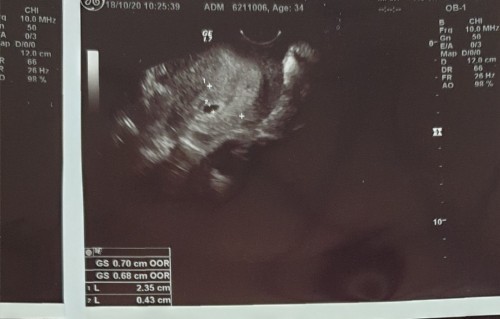

u/s 6week หมอบอกถุงเล็กมาก กังวลค่ะ

#ขอคำแนะนำหน่อยค่ะ ใครเคยมีประสบการณ์บ้างคะ กลัวท้องลม #ท้องแรกค่ะ